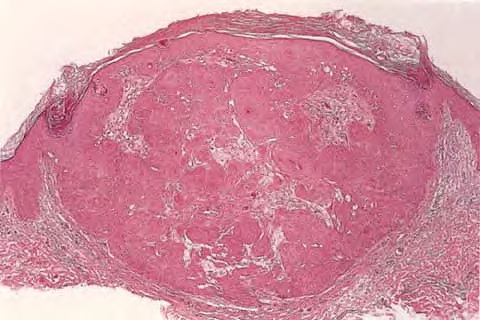

Inverted follicular keratosis = التقران الجرابي المقلوب